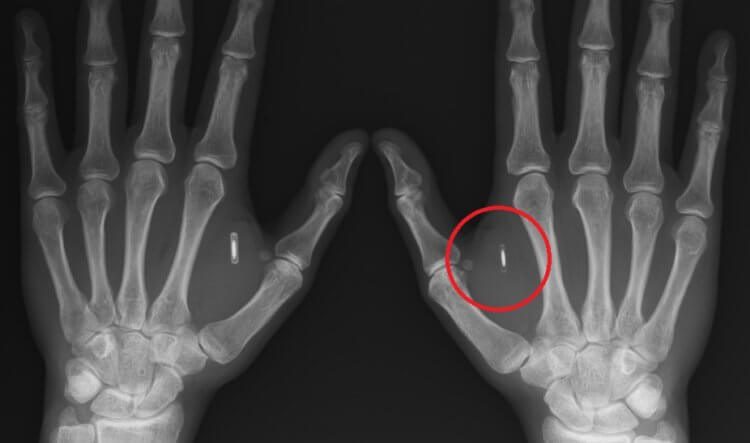

Чип под кожей человека можно заметить наощупь или на рентгеновском снимке

Операция по внедрению чипа в компании Epicenter занимает всего несколько секунд. Специалист вводит его в область между большим и указательным пальцами при помощи шприца и все — им можно пользоваться. Представители компании уверяют, что это безболезненная процедура, после которой даже не остаются шрамы. Заметить наличие чипа можно только наощупь, или на рентгеновском снимке. Чип не требует энергии и работает автономно, не причиняя вреда здоровью. Так, по крайней мере, говорят в компании Epicenter.